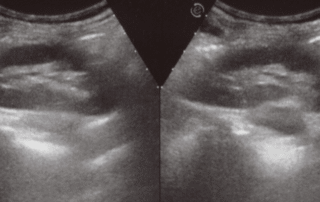

Erector Spinae Block

According to the National Library of Medicine, reporting on a [...]